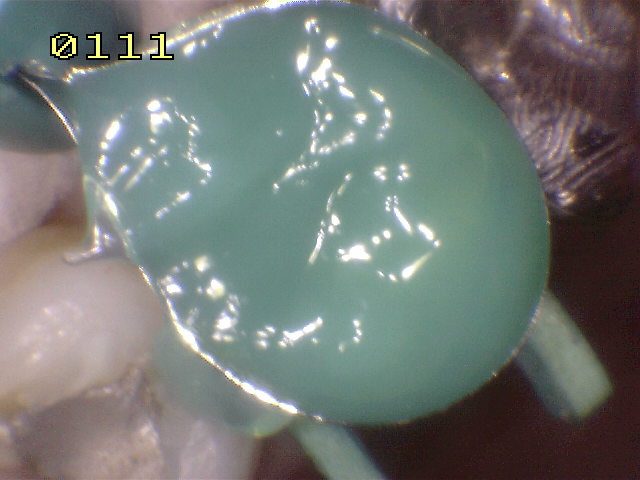

Se coloca

una matriz circular, se acuña y se bruñen los puntos de

contacto y por ultimo se graba con acido durante 30

segundos. |

Se seca

por 30 segundos, se aplica el agente de enlace y se

activa con luz halógena por 20 segundos. La resina

compuesta flow es aplicada en la caja mesial y

distal para fijar la matriz, una vez polimerizada. |